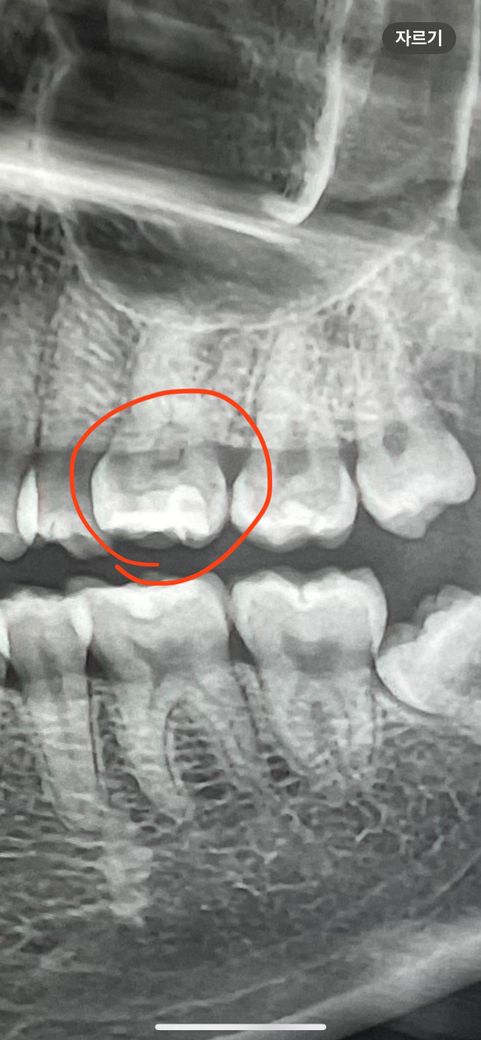

엑스레이 상에서 인레이와 크라운 중에서 어떤 치료가 필요한가요??

원래 인레이가 되어있던 치아인지는 모르겠어요.

충치로 인해 옆에 아주 살짝 깨진 부분이 보이고요.

사진으로만 봤을 경우에는 인레이로 치료를 하기에는 너무 넓은 범위인 것으로 보입니다. 인에이치료를 했을 경우 치아가 상대적으로 약해지게 되어 쉽게 파절되거나 할 수 있기 때문에 크라운 치료를 하는 것이 좋을 수 있습니다. 자세한 확인을 위해서 직화에서 진료를 받아보는 것을 권유 드립니다.

크라운을 해야할 가능성이 더 높아보이지만 인레이를 하는 것도 가능할 겁니다. 치실로 관리하시면 됩니다.

일단은 인레이를 해보시고 하고 나서 시린증상이 잇거나 충치제거시 신경이 노출되면 신경치료를 하셔야될것같습니다.